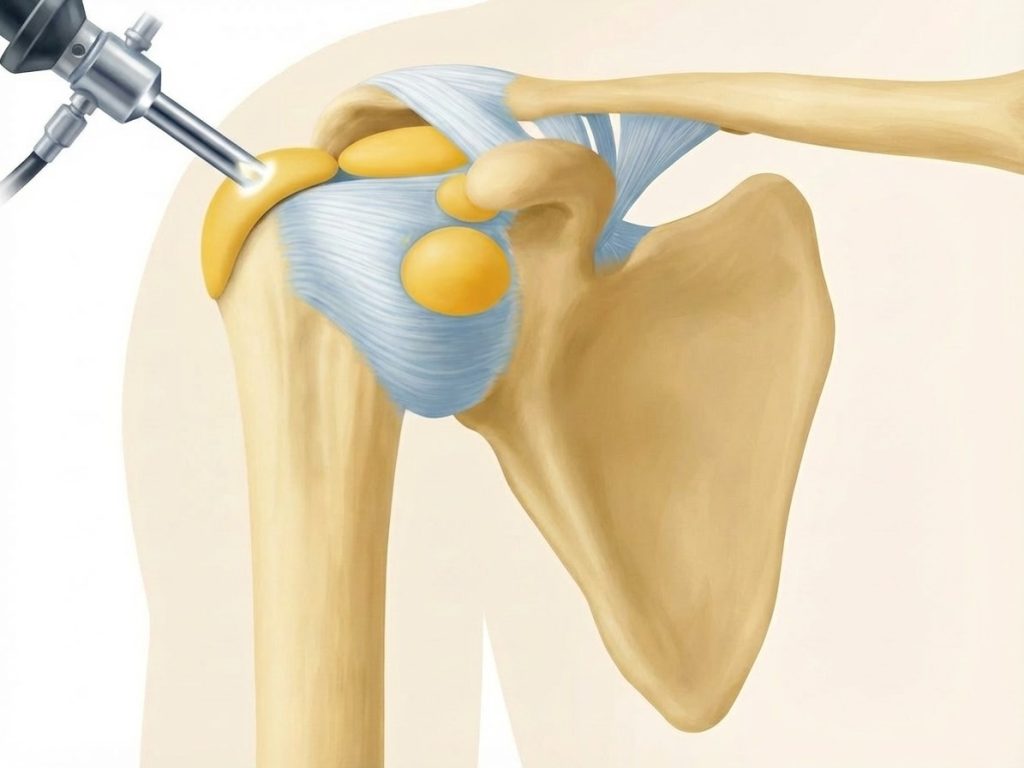

Zugang

• Einführung der Arthroskopkamera über den hinteren (posterioren) Zugang. Anlage eines weiteren vorderen (anterioren) Portales.

• Inspektion des Glenohumeralgelenks und des Subakromialraums, des Schleimbeutel und der Rotatorenmanschette

Darstellung des AC- Gelenkes

• Abtragen von Bursa und Weichteilen über dem AC-Gelenk

• Schonung der Kapsel und der coracoclaviculären Bänder (wichtig für Stabilität!)